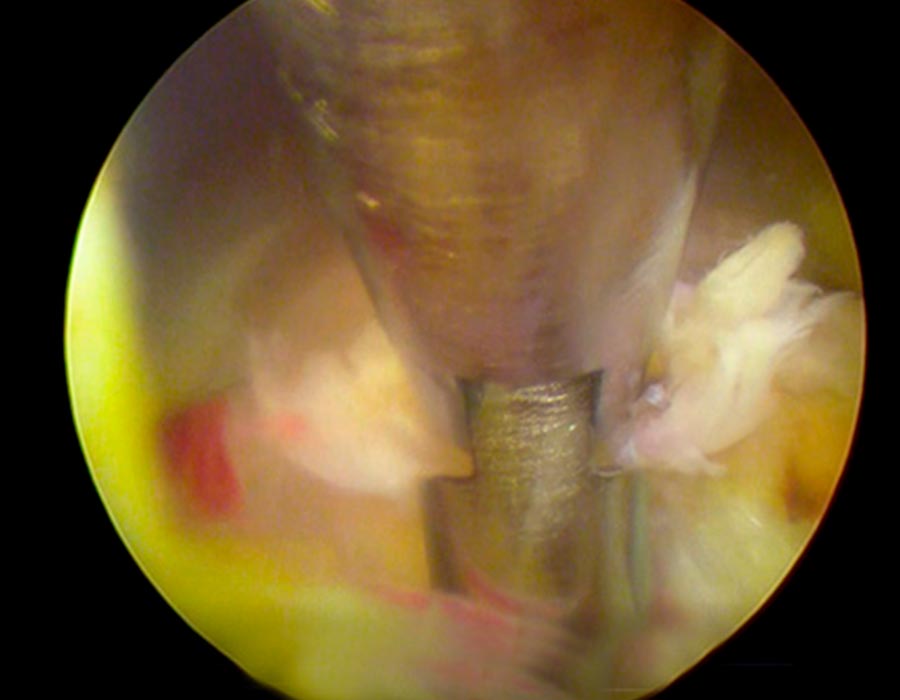

Se realiza una incisión de 3mm en la parte correspondiente de la espalda y, sin producir ningún daño en los tejidois, accedemos al área afectada, directamente al canal de la vértebra lumbar.

Tras localizar la zona de trabajo, suavizamos la hernia y procedemos a su retirada y al posterior sellado tanto del disco como del anillo donde ha salido la hernia para evitar futuras fugas.